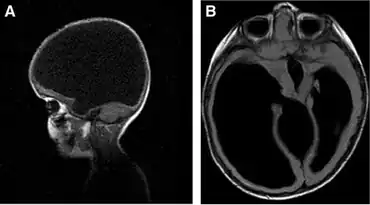

Hydranencephaly

Hydranencephaly is a condition in which the cerebral hemispheres are missing and instead filled with sacs of cerebrospinal fluid. People are born with hydranencephaly, but most of the time, the symptoms appear in a later stage. Newborns with hydrancephaly can swallow, cry, sleep and their head is in proportion to their body. However, after a few weeks, the infants develop increased muscle tone and irritability. After a few months, the brain start to fill with cerebrospinal fluid (hydrocephalus). This has several consequences. Infants start to develop problems with seeing, hearing, growing, and learning. The missing parts of the brain and the amount of cerebrospinal fluid can also lead to seizures, spasm, problems with regulating their body temperature, and breathing and digestion problems. Besides problems in the brain, hydranencephaly can also be seen on the outside of the body. Hydrocephalus leads to more cerebrospinal fluid in the brain, which can result in an enlarged head.[9][10][11]

The cause of hydranencephaly is not clear. Hydranencephaly is a result of an injury of the nervous system or an abnormal development of the nervous system. The neural tube closes in the 6th week of the pregnancy,[12] so hydranencephaly develops during these weeks of the pregnancy. The cause of these injuries/development is not clear.